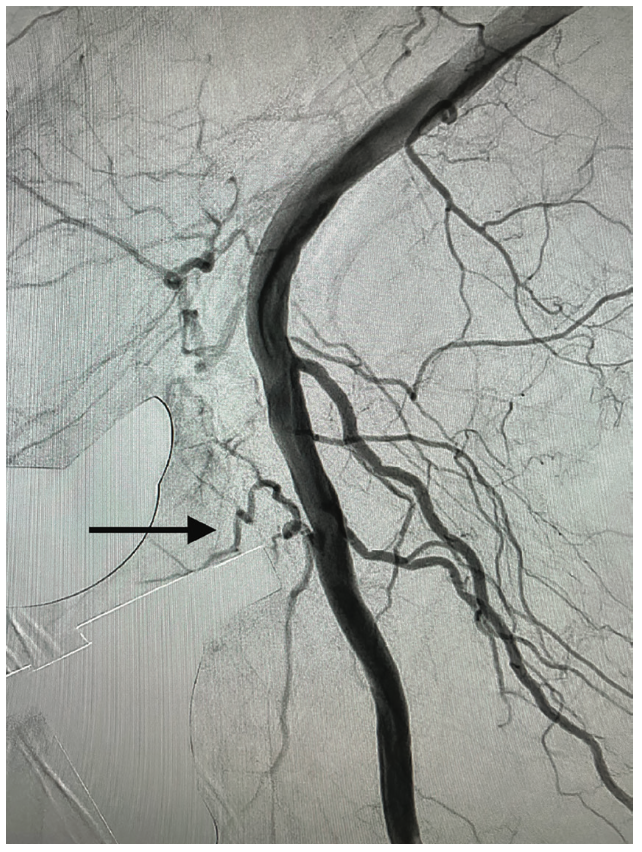

The left common femoral artery was accessed, the right external iliac artery was selectively engaged, and an angiogram was performed for delineation of the popliteal artery and its branches (Figure 2). Transpedal access was then obtained to the right anterior tibial artery for a better approach to the acute upward angle takeoff of the inferior genicular artery. A multipurpose catheter was then advanced to the level of the P2 segment of the popliteal artery. Using a combination of an .014 Advantage Glidewire (Terumo Interventional Systems) and Cantata Microcatheter (Cook Medical), the lateral inferior genicular artery was selected and the catheter was advanced to the intraluminal position. Two coils, a 2 mm x 7 mm Nester coil (Cook Medical) and then a 2 mm x 2 mm Nester coil, were deployed in standard fashion (Figure 3). Subsequent angiography showed successful coiling of the lateral inferior genicular branch. The microcatheter and multipurpose catheter were removed (Figure 4). Hemostasis was obtained using manual pressure for the right transpedal access and Angio-Seal (Terumo Interventional Systems) for the left femoral artery.